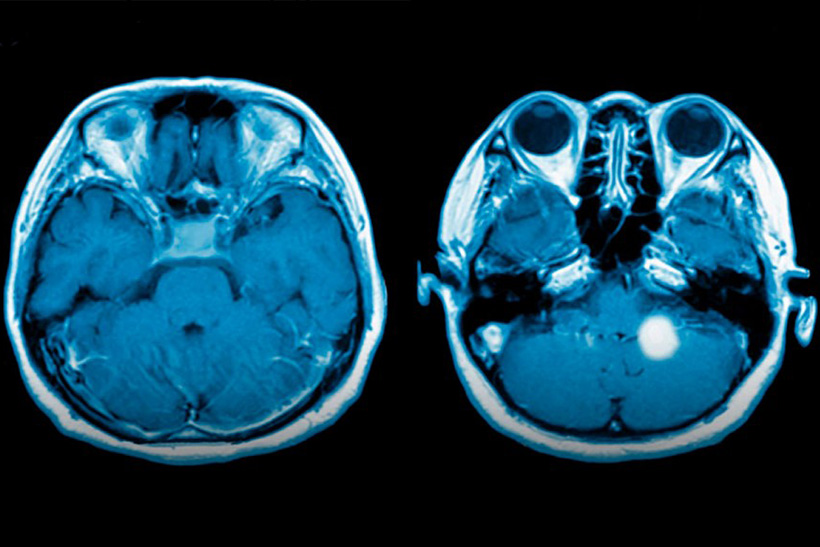

Debido a sus cualidades, además de como veneno neutrónico, el gadolinio ha encontrado múltiples aplicaciones: en microondas, en los tubos de imagen de televisores a color y también como agente de contraste radiológico intravenoso en la resonancia magnética (RM).